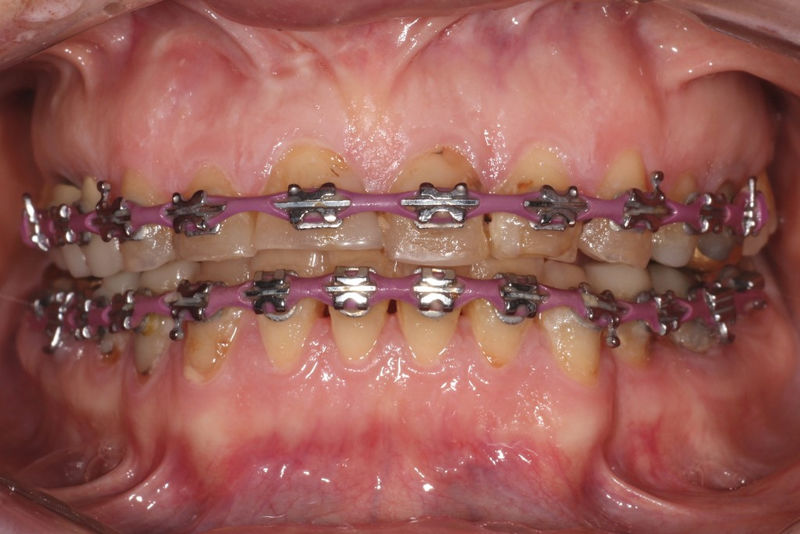

Implantes, ortodoncia y coronas.

Ortodoncia y coronas.

Cirugía ortognática, implantes, carillas y coronas,